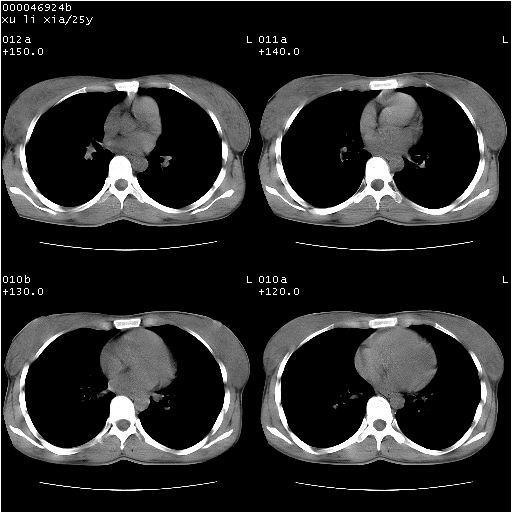

患者 女,25岁。因“左侧卵巢肿瘤”术前胸片偶然发现两肺病变。平素无明显不适,无呼吸系统症状及体征,无传染病史。

胸部ct轴位平扫(层厚10mm,螺距1.5,重建间隔10mm),图像如下:

病灶呈地图样分布于肺外围,与正常组织分界清晰+弥漫性磨玻璃影中见小叶间隔增厚呈碎石路样表现+年轻女性,无明显临床症状=肺泡蛋白沉积症?

病灶呈离心性分布,以两上肺多见,远离肺血管纹理,有部分肺间质条索影,病人症状轻微,考虑结节病。